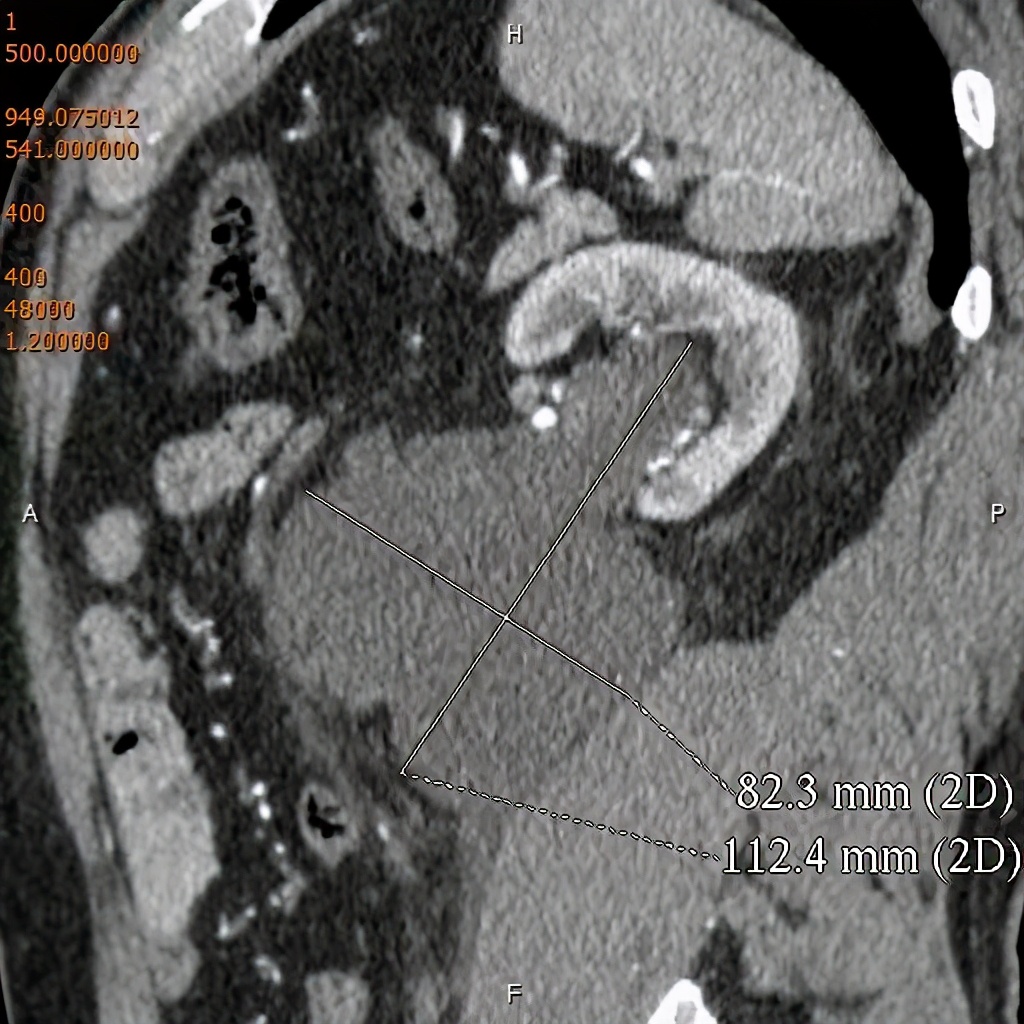

上图所示:体检B超示(右)肾积水,行CT尿路造影检查。左图示平扫后重建示(右)肾囊肿向肾盂内突出。右图示,静脉注入造影剂、经过一定时间延迟后,(右侧)输尿管起始处造影剂充盈良好,肾盂内囊肿内未见造影剂填充。 (二)肾外肾盂: 正常人肾盂大多位于肾窦内,成为肾内肾盂;少数位于肾窦外,成为肾外肾盂。肾外肾盂属于正常肾盂的一种情况,可见于任何年龄。